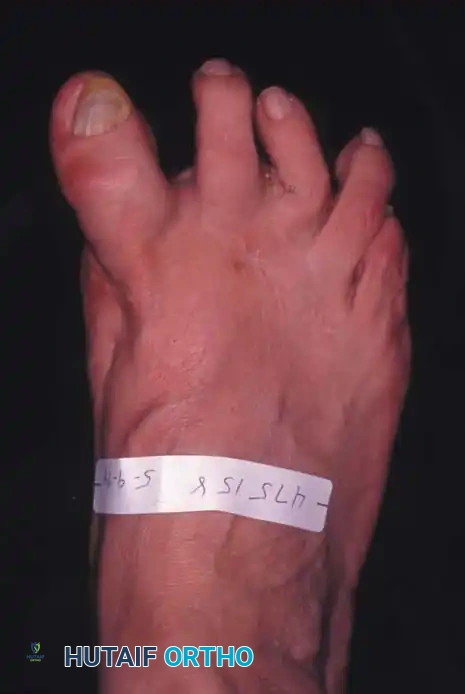

Keller Resection Arthroplasty The Keller procedure combines resection hemiarthroplasty of the fi rst metatarsophalangeal joint with removal of the medial eminence of the fi rst metatarsal (Fig. 78-28). Although removing the base of the proximal phalanx decompresses the joint and mobilizes the hallux, allowing marked correction of valgus, the varus of the fi rst metatarsal is not corrected, and maintaining correction of the valgus of the hallux is diffi cult. Other complications of the Keller procedure have been emphasized in the literature to such an extent (with neither the incidence nor the severity of such complications clearly documented) that the indications for this procedure have been limited severely. In our experience, however, complications are uncommon if patients are selected carefully. Modifi cations in the original technique also have allowed expansion of the indications for the Keller bunionectomy. Candidates for the Keller procedure are patients older than 50 years with moderate-to-severe hallux valgus (30 to 45 degrees); intermetatarsal angles of 13 degrees or less, indicating mild-to-moderate metatarsus primus varus; and pain over the medial eminence with any shoe worn, so the variety of shoes the patient can wear is severely limited. An incongruous fi rst metatarsophalangeal joint caused by

Fig. 78-26 Modifi ed McBride bunionectomy (DuVries; Mann). A, Medial capsule of second metatarsophalangeal joint is sutured to lateral capsule of fi rst metatarsophalangeal joint with interposition of released adductor hallucis. B, Medial capsular resection. C, Confi guration after capsular resection. D, After capsular imbrication, hallux should rest in neutral position or not exceed 5 degrees of varus. E, Postoperative dressing technique (Mann). ( E after Beverly Kessler; courtesy of LTI Medica and The Upjohn Company.) lateral subluxation of the phalanx on the metatarsal head, severe lateral displacement of the sesamoids, and any evidence of degenerative cartilage changes in the joint all are radiographic indications for the Keller procedure. Two modifi cations in technique can expand these indications, however, to include patients with more severe deformities (Fig. 78-29) (but not to include younger patients): fi bular sesamoidectomy and lateral displacement of the fi rst metatarsal. Using these modifi cations, Donley et al. obtained an average 18-degree correction of the metatarsophalangeal angle and an average 6-degree correction of the intermetatarsal angle in 38 patients (50 feet);

95% of patients were satisfi ed with their results. Patients with 50 degrees or more of valgus of the hallux (18 to 20 degrees of varus of the fi rst metatarsal), complete lateral dislocation of the sesamoids, marked degenerative changes, and severe pronation of the hallux may benefi t functionally and cosmetically from alterations of the standard technique.

D

Fig. 78-29 Severe hallux valgus with bursa formation in 70-year-old woman. A and B, Anteroposterior and lateral clinical photographs of patient’s right foot. C, Correction of deformity by modifi ed Keller procedure. D, Preoperative and postoperative weight bearing radiographs of same patient.